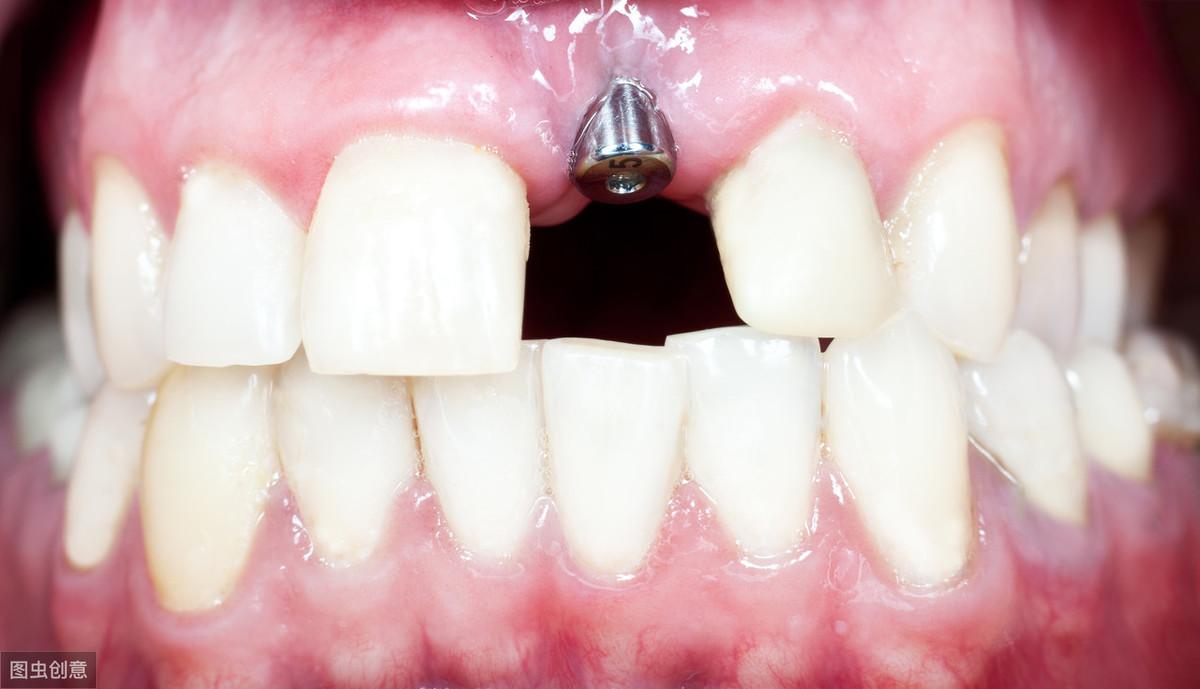

種植牙技術是近幾十年出現(xiàn)在大眾視野中的一種修復缺失牙體的方法。一顆完整的種植牙體由三部分組成:種植體、基臺、人工牙冠。

手術過程就是將種植體植入患者的牙體缺失處,待其傷口愈合,種植體與牙槽骨結合牢固后,將基臺安裝在種植體上,再將人工牙冠安裝在基臺上,形成完整而堅固的人工牙體。

種植牙技術就像在缺失牙體處種一顆新的牙齒,能夠和牙槽骨結合,做種植牙能有預防牙槽骨萎縮,這是普通的假牙無法做到的,而且種植牙體不依附周圍鄰牙,對鄰牙不造成任何負擔,所以相對其他修復手段,不僅更為牢固不易松動,且使用壽命長,果好。